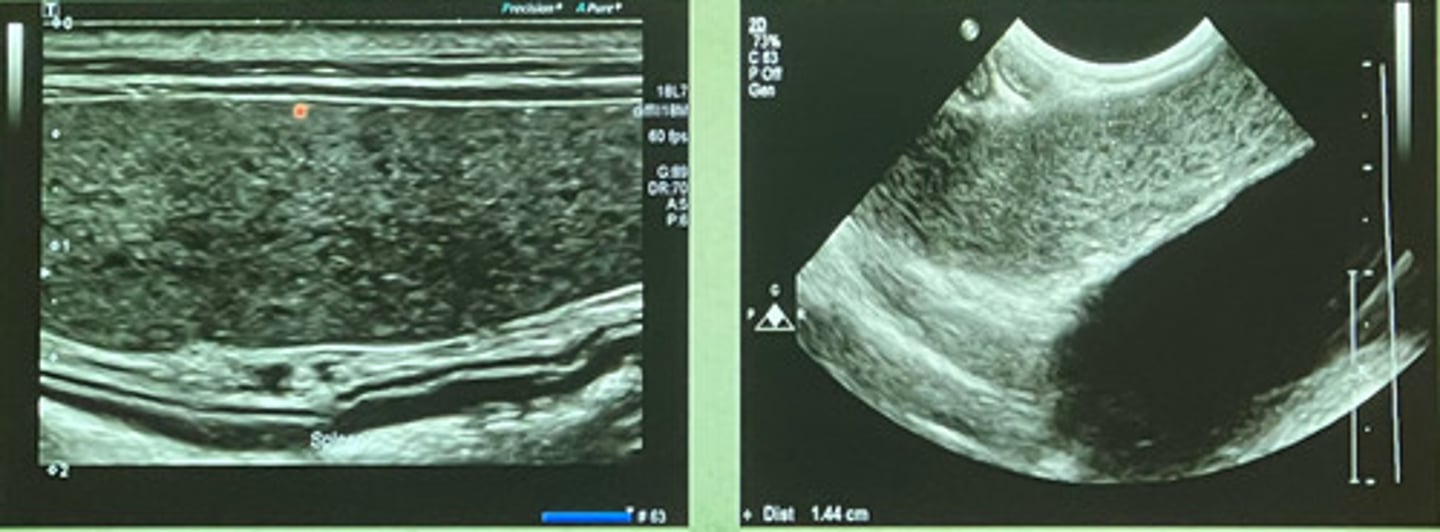

this is the spleen, just know what it looks like!!

what type of tool is being used in this ultrasound to see the different vessels?

yes, from surrounding fat

is this shadowing near the spleen normal?

shadowing underneath the mass

if there is a hyperechoic mass in the spleen, what artifact will occur due to it?

shadowing due to the splenic mass

what are the arrows indicating? (there is a mass in this spleen)

focal

are these ultrasound images of the spleen focal or diffuse?

diffuse

are these ultrasound images of the spleen focal or diffuse?